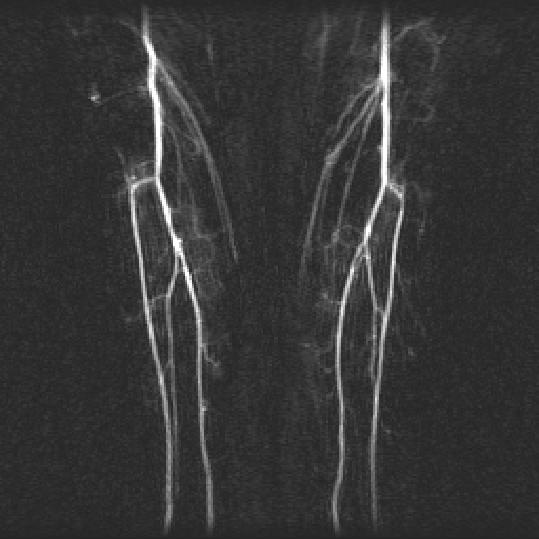

ManualDSA

AutoDSA

For time-resolved background-subtracted contrast-enhanced magnetic resonance angiography, the bright and sparse arterial signal allows unique identification of contrast bolus arrival in the arteries. This paper presents an automatic filtering algorithm using such arterial characterization for selecting arterial phase images and mask images to generate an optimal summary arteriogram. A paired double-blinded comparison demonstrated that this automatic algorithm is as effective as the manual process.